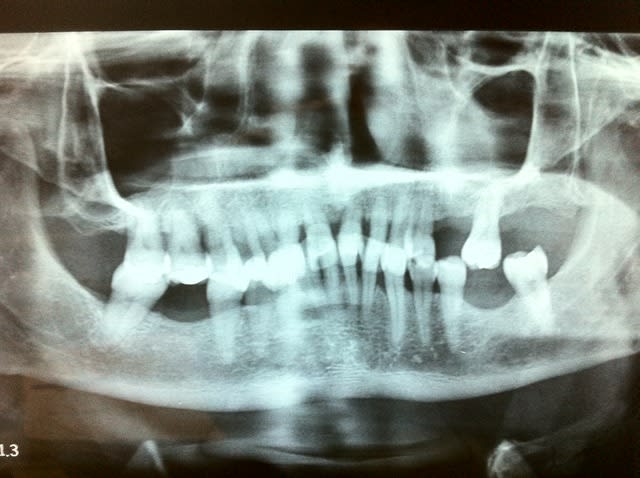

DV effondrée, mord sur la papille incisive maxillaire, 13 à 23 vestibulées, facettes d'usure au collet de 11/21 en palatin, dents mobiles, etat paro trés dégradé, mobilités moins importantes qu'on pourrait croire mais quand même.

Vestibulo-version des incisives maxillaires avec aspect en éventail typique des parodontites chroniques, confirmé par le niveau osseux uniforme sur la pano et les mobilités évoquées.

> parodontites chroniques, confirmé par le niveau osseux uniforme sur la pano et

> les mobilités évoquées.